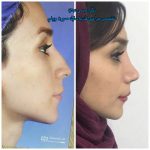

– متخصص جراحی فک , پلاستیک صورت و بینی

جراحی فک , پلاستیک , صورت وبینی

جراحی ترمیمی و زیبایی فک و صورت و جمجمه و گردن